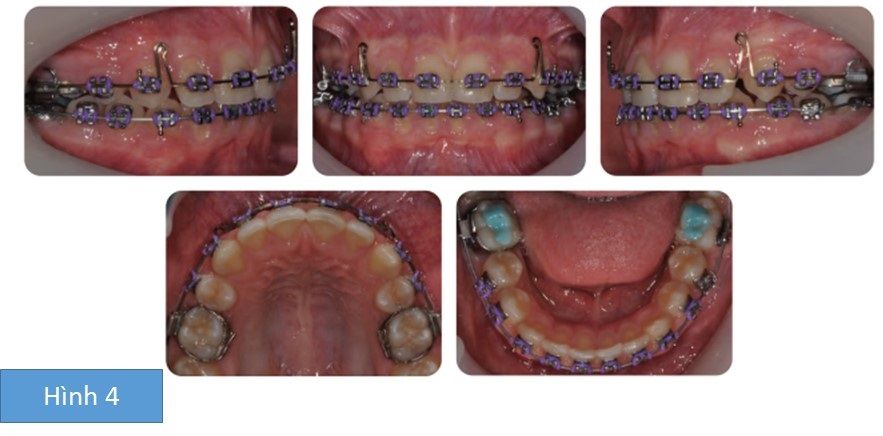

Phân tích case: Niềng răng thành công cho bệnh nhân 10 tuổi có các răng số 5 mọc ngầm và R21 chết tủy

Bệnh nhân nam 10 tuổi có bộ răng hỗn hợp, có tương quan răng cửa hạng I trên kiểu xương hạng I với các kích thước dọc trung bình, phức tạp bởi:

- Các răng hàm nhỏ thứ 2 mọc ngầm ở cả 2 cung hàm trên và dưới

- Tương quan răng hàm lớn hạng II hai bên

- Cắm trùm tăng

- Các răng hàm nhỏ thứ nhất hàm dưới xoay

- R21 chết tủy